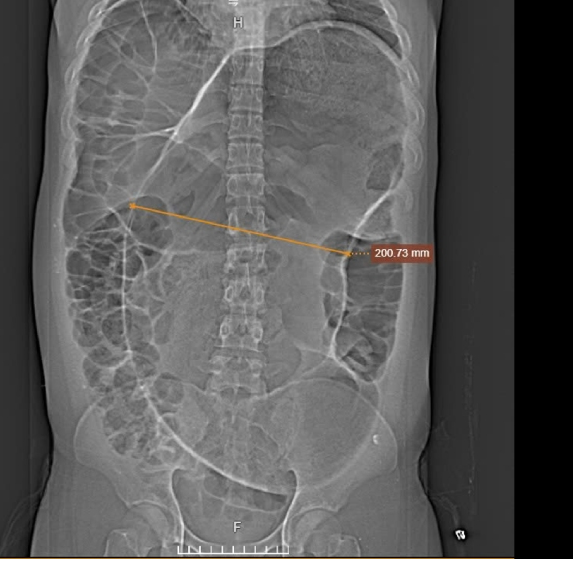

Hình chụp cắt lớp vi tính cho thấy đoạn đại tràng căng to (mũi tên vàng) - Ảnh: Bệnh viện Đa khoa Tâm Anh

Thạc sĩ bác sĩ Nguyễn Thanh Biên, Trung tâm Nội soi và Phẫu thuật Nội soi Tiêu hóa, Bệnh viện Đa khoa Tâm Anh cho biết, kết quả chụp CT 1975 lát cắt ghi nhận đại tràng sigma (đoạn cuối của đại tràng) bị xoắn, cuộn tròn mạch máu mạc treo và quai ruột đại tràng sigma, đường kính 20 cm, to hơn gần 7 lần bình thường, lòng ruột chứa đầy khí và cặn bã, thành ruột mỏng.